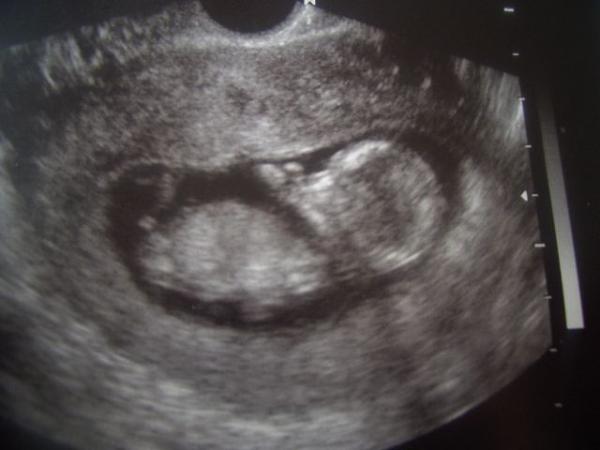

und das ist aus der 14 SSW da wurde über den Bauch geschallt

In der 12 SSW war ich ausserplanmäßig beim FA,da hatte ich morgens so starke Unterleibsschmerzen fast wie wehen,da hatte ich irgentwie ein ungutes Gefühl gehabt und bin dann zum FA. Der hat gesagt das es ein wachstumsschub der Gebärmutter war. Und in der 14 SSW hatte ich ganz normal VU gehabt.